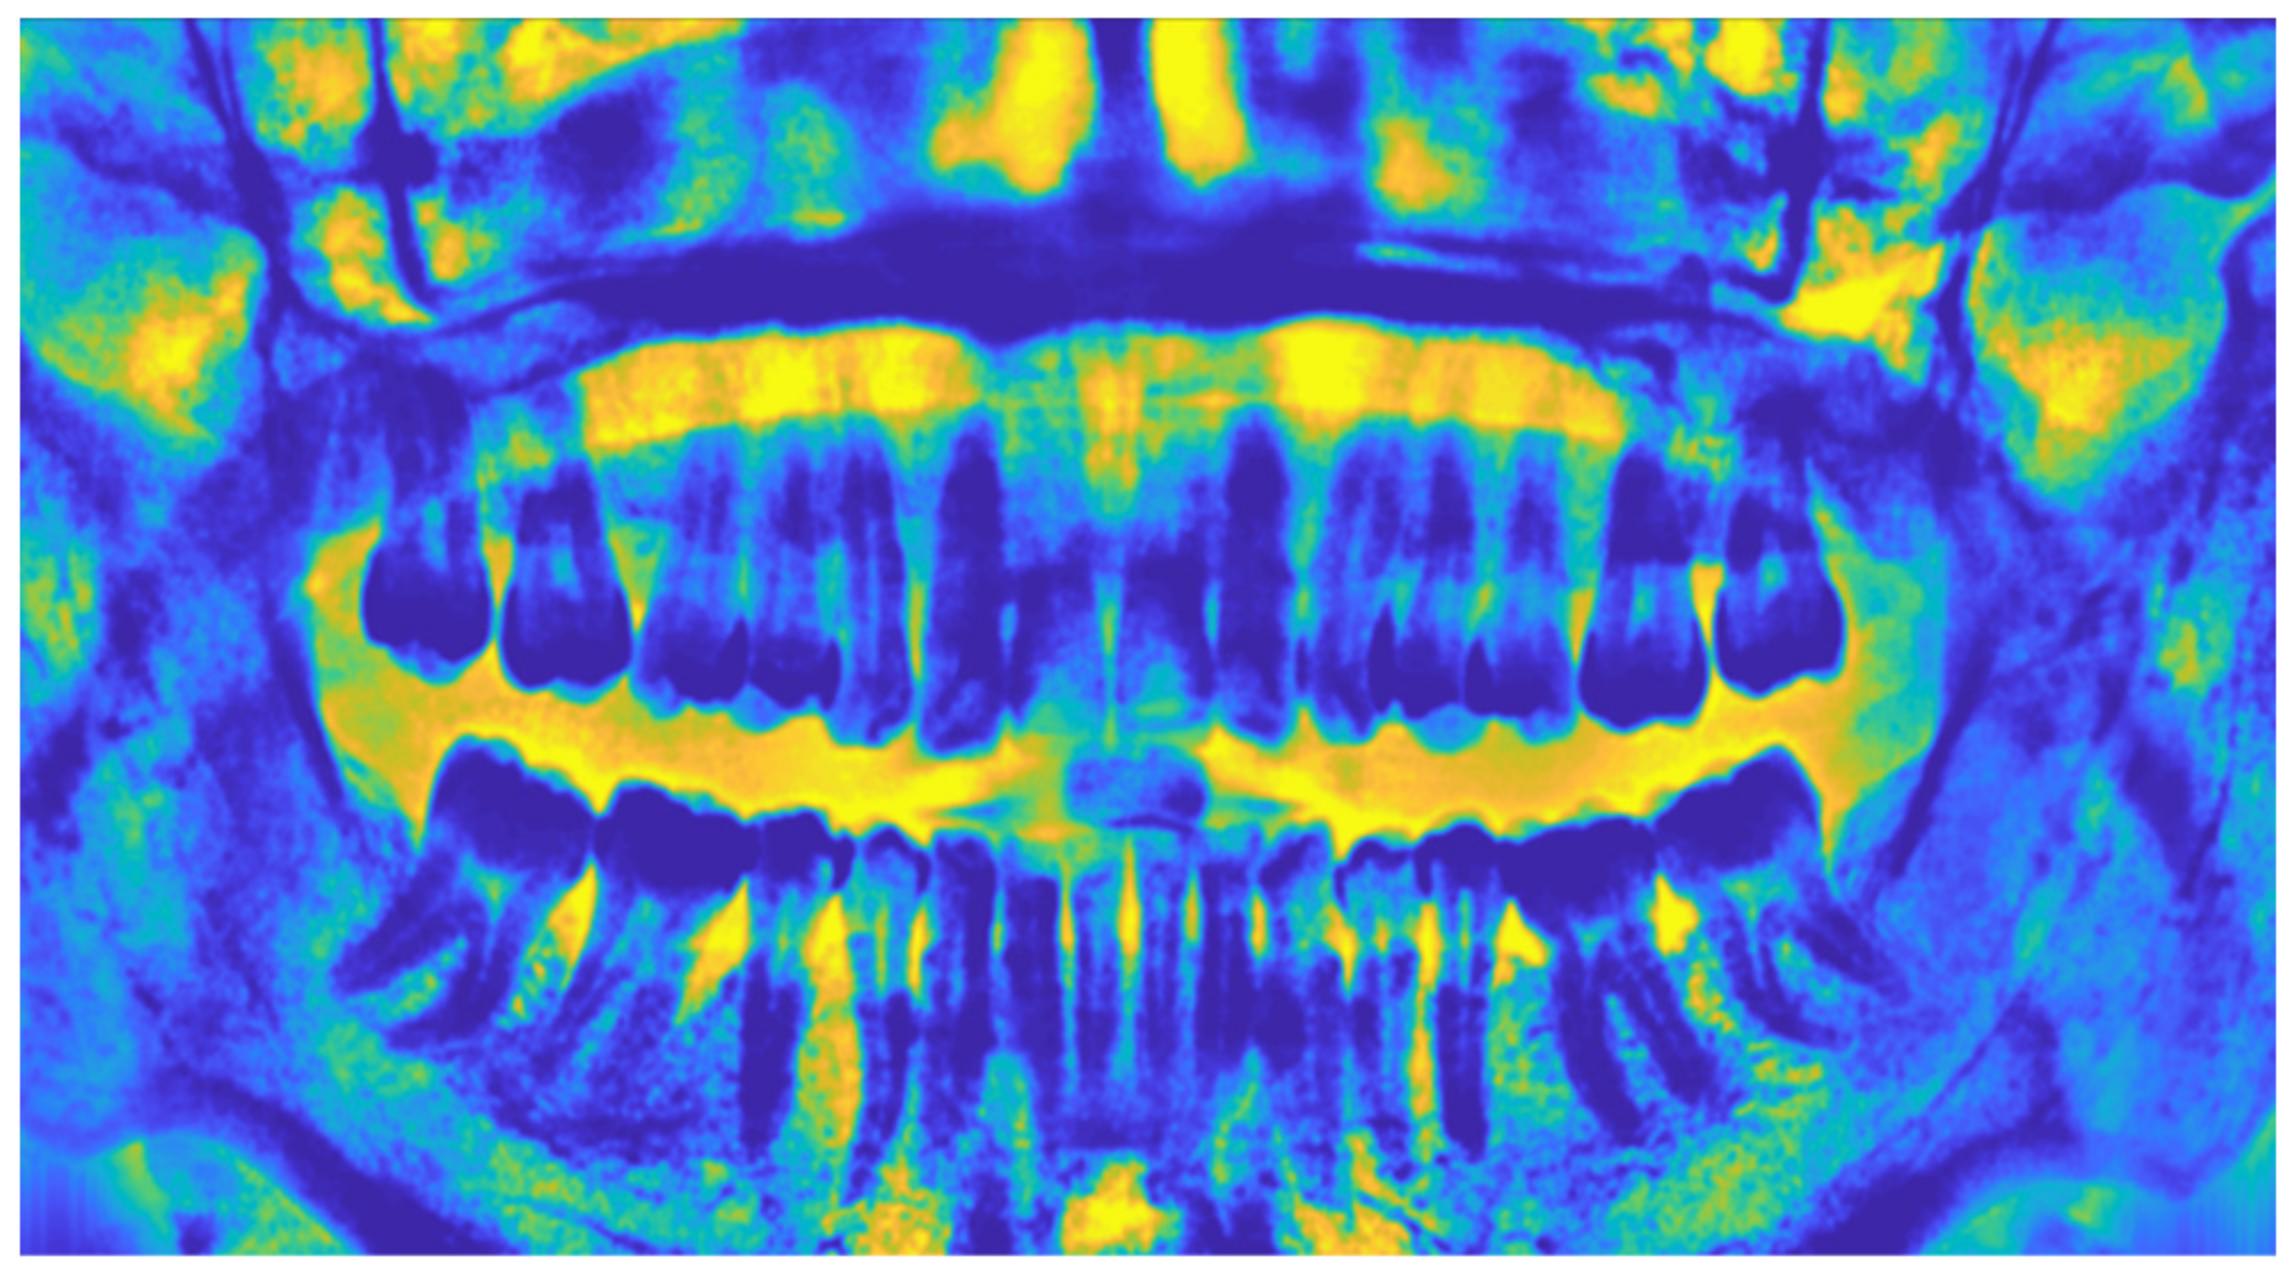

2.1.4. Adaptive Histogram Equalization

3. Results